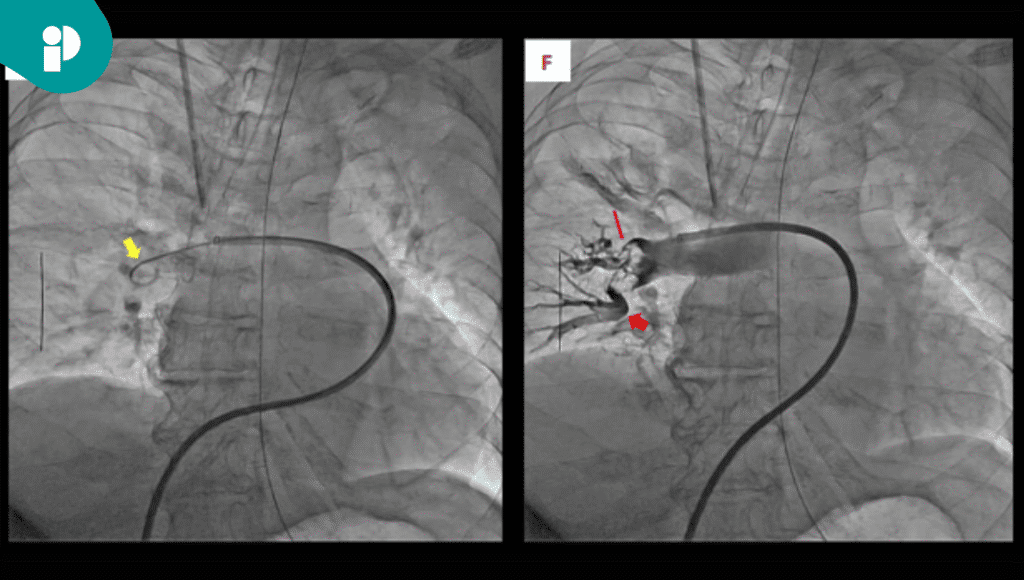

Pese a la administración inicial de anticoagulantes y trombolíticos, su condición no mejoró, por lo que el equipo médico decidió realizar una terapia dirigida por catéter (TDC). A falta de dispositivos especializados, se optó por utilizar catéteres convencionales —como un catéter guía PTCA y un catéter pigtail— para llevar a cabo la trombectomía, trombólisis y fragmentación del trombo.

Durante el procedimiento, los signos vitales de la paciente empeoraron temporalmente debido a una embolia distal, complicación que fue manejada exitosamente con la administración rápida de líquidos. Cuatro días después, la paciente se recuperó del shock cardiogénico y posteriormente fue dada de alta tras un reemplazo femoral exitoso.